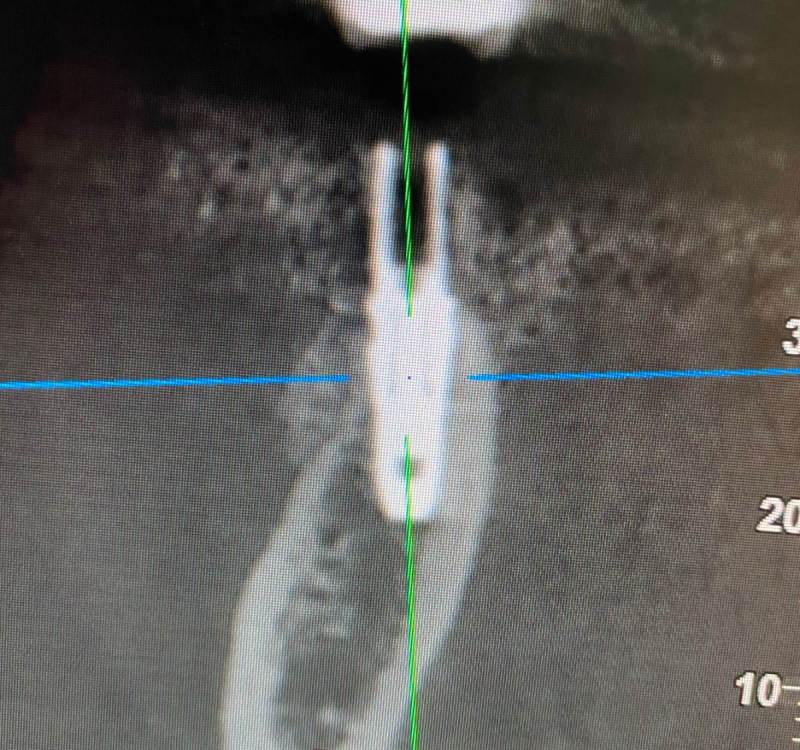

kriokov Опубликовано 14 июля, 2022 Поделиться Опубликовано 14 июля, 2022 суперлайн, простоял 3 года, кутил одномоментно с удалением. Снимки в один день , 20 год, интервал 20-30 секунд, чуть другая проекция. До этой терминальной стадии и жалоб то не было. Пришел с подвижностью коронки. Ортопед сказал , что абатмент вроде как премилл из фрезерного центра. Фрезой выпиливал, жесть. 1 Ссылка на комментарий

колесников Опубликовано 14 июля, 2022 Автор Поделиться Опубликовано 14 июля, 2022 (изменено) 12.07.2022 в 07:48, Astronaft сказал: Это хорошай заговор-пожелание. В жизни часто не так. По одной простой причине общее здоровье человека влияет намного сильнее. Пародонтологический статус - если есть карманы хоть 5-6мм где-то во рту риск пери-имплантных явлений возрастает. Микробиота слюны, вязкость, диета, качество гигиены, обший воспалительный фон- это сфера влияния пациента. Качественное местное исполнение это хороший фундамент - только одна из составляющих. Астра Профаил - укороченный, асимметричый конус. 3мм с одной стороны, 2мм с другой. Конфигурация перелома закономерна - сами абатменты раскололи высокую стенку от низкой. Я бы предположил что тещины первичны, резорбция это следствие. Приветствую! Инфекция,карманы,несостоятельные конструкции имели место быть,равно как и мост на профайлах во 2ом секторе. С которым все экстремально в плане протетики и идеально по костному объёму . Завтра панораму выложу. Относительно оси нагрузки не могу согласиться,прелесть профайла именно в правильной ортопедической позиции. Платформа не имела вестибулярной позиции и ангуляции. Однозначно причиной фрактуры и ангуляции была резорбция. Что было причиной резорбции-вопрос. Если учесть что аугментации была в успешной(это можно заметить в промежуточном сегменте Изменено 14 июля, 2022 пользователем колесников Ссылка на комментарий

колесников Опубликовано 14 июля, 2022 Автор Поделиться Опубликовано 14 июля, 2022 11.07.2022 в 11:17, TIGER сказал: тут ожидаемо,недозаглуб,grade4 конус ....и закономерный финал,иесли там винтовая с уровня имплантов то вообще картина маслом Первое фото-это следствие. Импланты были заглублены на 1мм,костное ложе профилировано и ремоделировано. Была немедленная нагрузка. На момент фиксации постоянной конструкции патологические изменения отсутствовали. Перегруз приводит к резорбции кости-это очевидный факт. Ишемия первична,инфекция вторична. Ссылка на комментарий